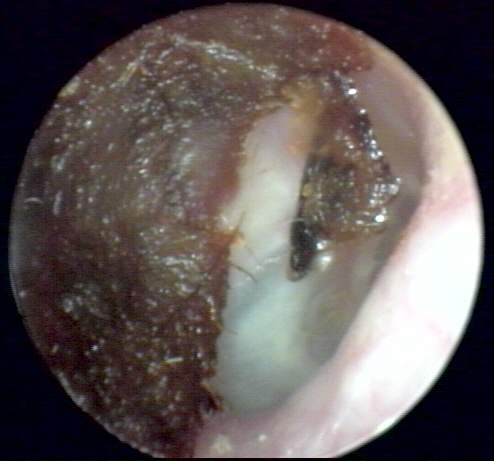

+3: Occlusive major amount present; likely to interfere with insert and circumaural hearing testing, may add a conductive overlay; obstruct hearing aid receiver and vent, reducing effective gain and output. Tympanic membrane not visualized. Removal essential. EXAMPLES:+3/A(25k) | +3/B(27k) | +3/C(27k) | +3/D(17k) | +3/E(19k) | +3F(18k)